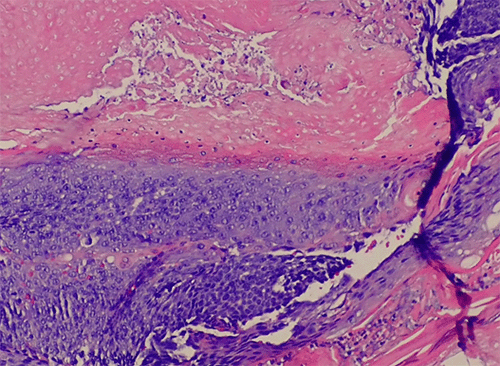

The patient tolerated the surgical procedure well without any perioperative complications. Pathologic examination revealed a formalin-fixed, 1.4 × 0.7 × 0.7 cm tan-red mass with a red-to-white, gritty cut surface. Histopathologic analysis demonstrated two distinct cell types: a basophilic cell type with mitotic figures and indistinct cell borders, and an eosinophilic cell type lacking nuclei and exhibiting more distinct borders. Additionally, multinucleated giant cells were noted within the surrounding tissue (Figure 3).

Figure 3. Histopathology of Excised Specimen (H&E Stain). Published with Permission

(A) Low-power magnification reveals a lobular, partially cystic lesion with a thick, fibrous capsule (dark blue arrows)

(B) Higher magnification shows an island of epithelial cells with basophilic cytoplasm transitioning into shadow/ghost cells in the central region of the tumor

Histopathological hallmarks of PMC include islands of epithelial cells made up of basophilic cells, a transformation zone to eosinophilic shadow or “ghost” cells, and calcification.7,9,10,12 Additionally, studies have indicated that PMC tumors are often encapsulated in a thick layer of fibrous tissue.16,17 All of these histological markers except calcification were noted in our patient’s tumor (Figure 3).

The morphological progression of PMC is theorized to occur in stages. The first (“early”) stage is characterized by a small, cystic tumor. This progresses to the “fully developed” stage, with a larger, more cystic tumor and basophilic cells at the periphery. The “early regressive” stage is marked by islands of basophilic cells, shadow/ghost cells, and multinucleated giant cells. The final (“late regressive”) stage is characterized by a lack of basophilic and giant cells with calcification and ossification.18 Based on the histopathological findings, our patient’s PMC appears to have been in the “early regressive stage” at the time of diagnosis.